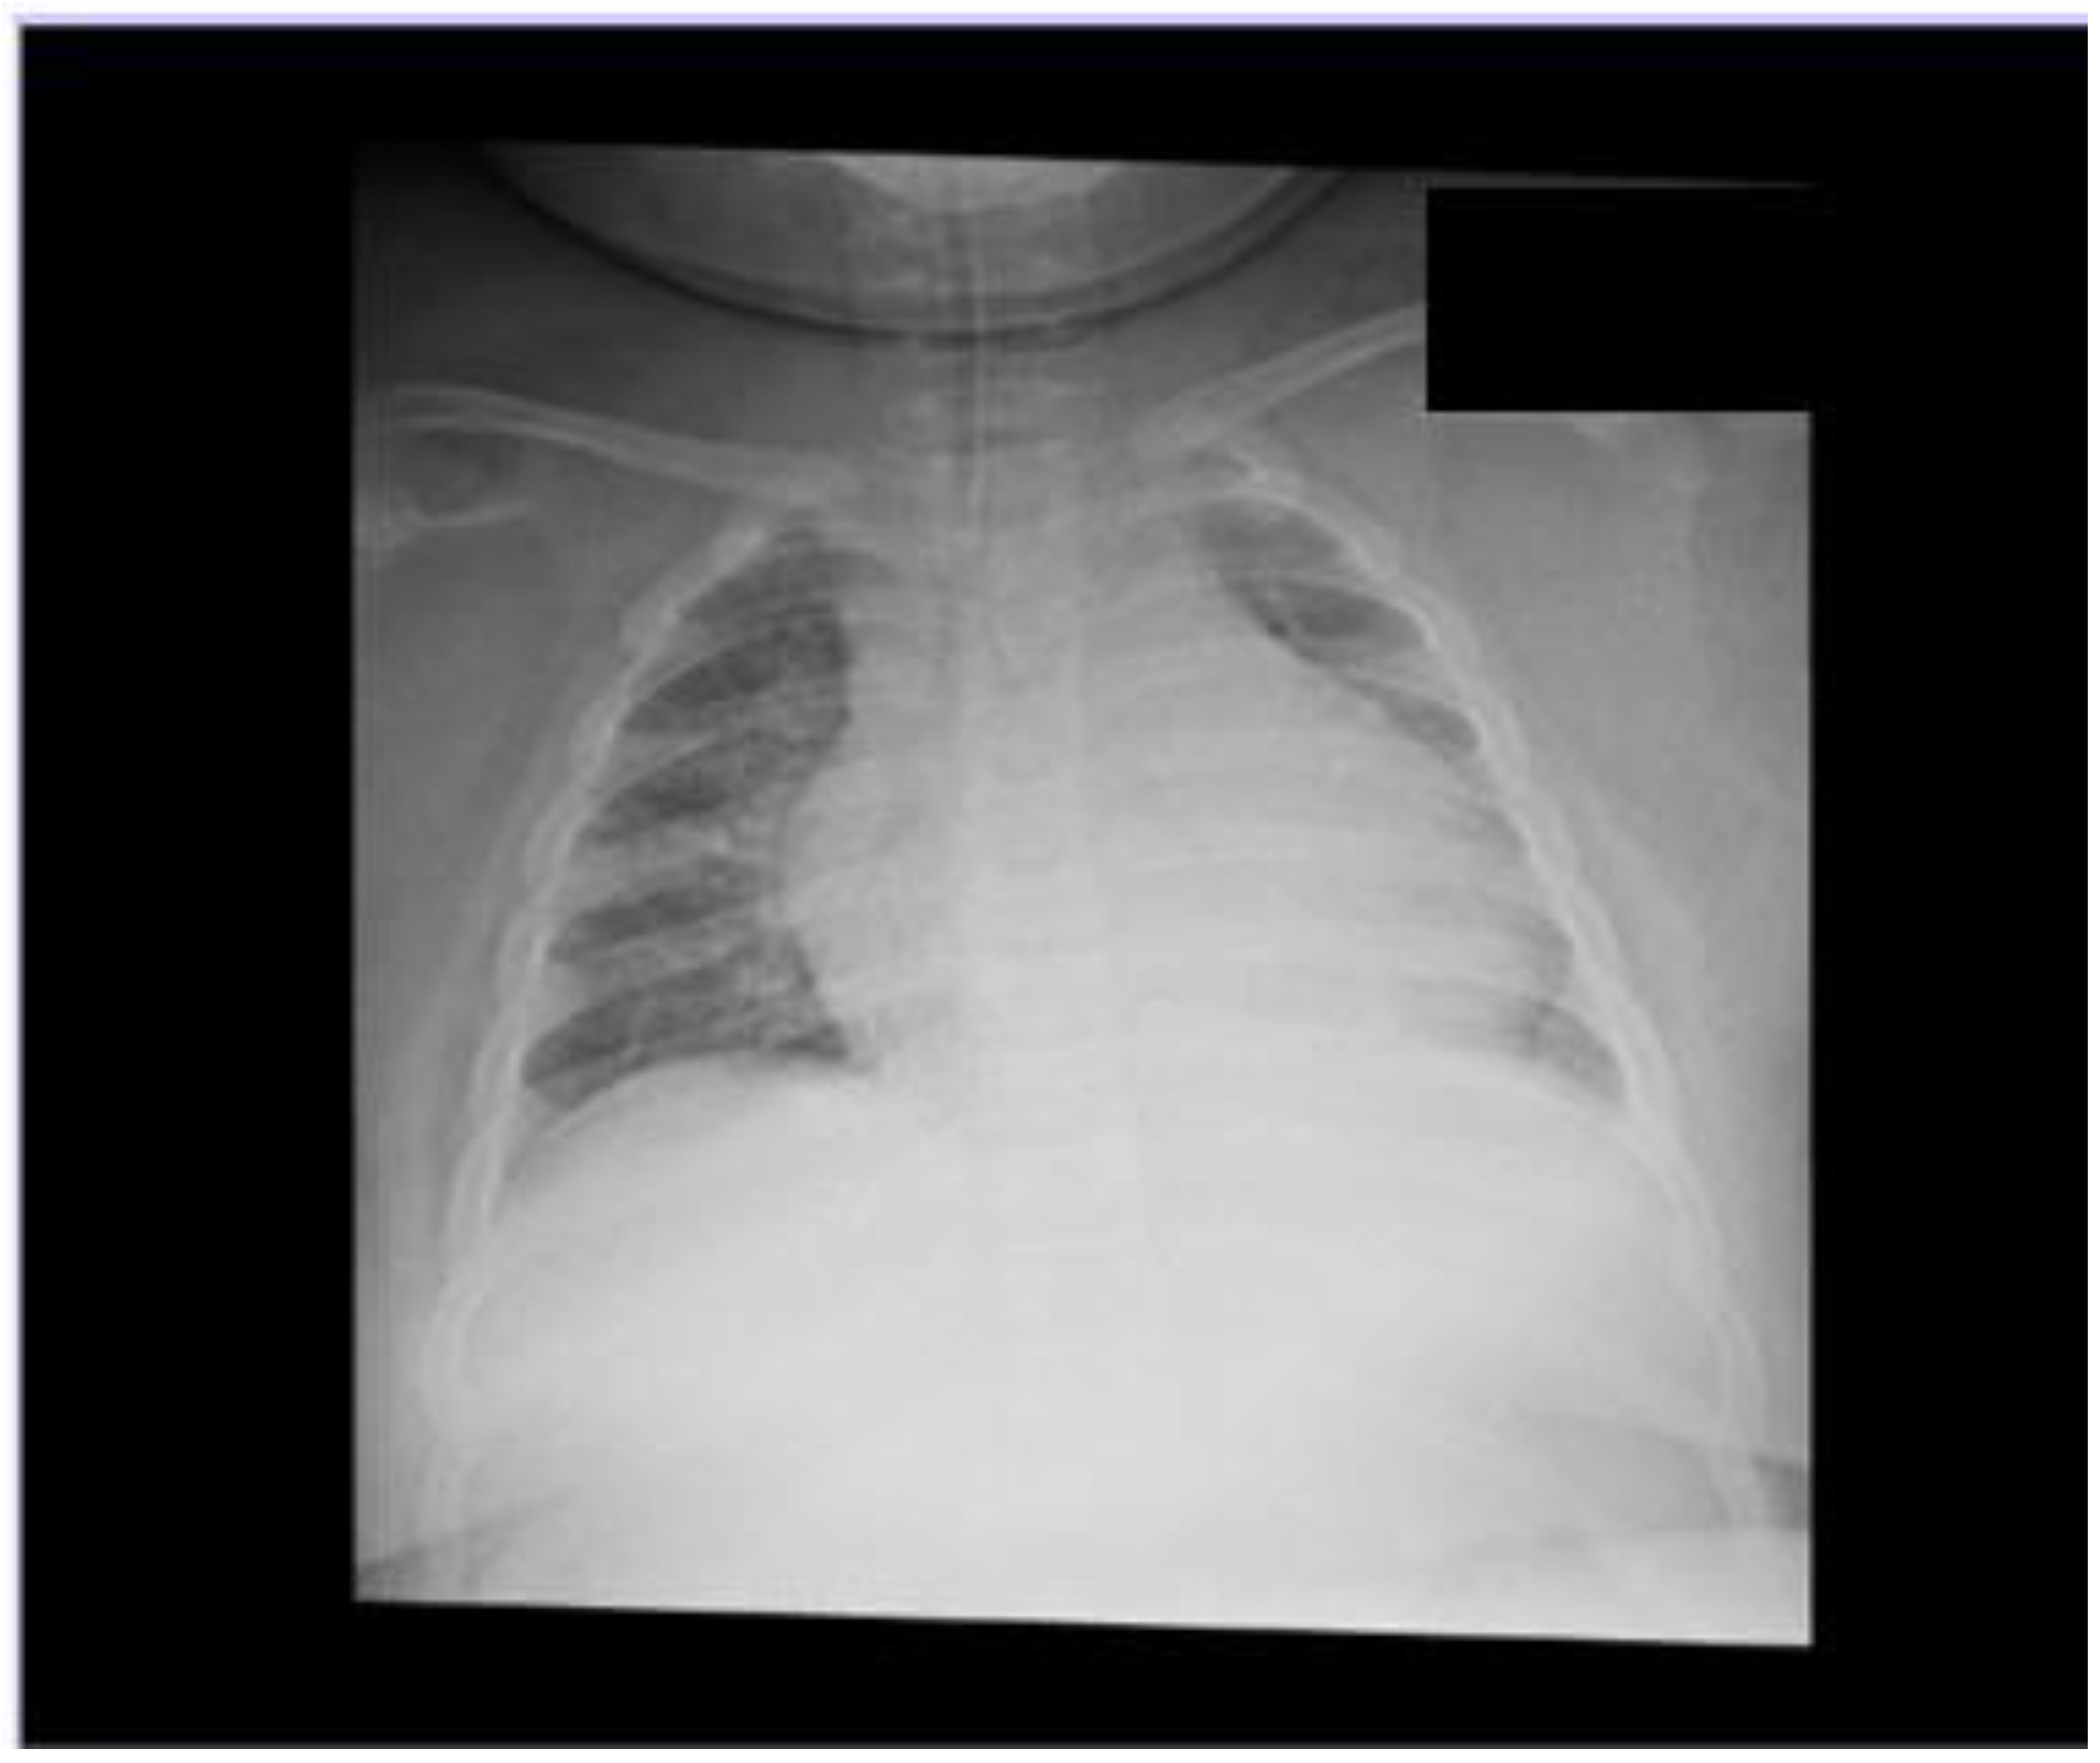

2.1. First Clinical Case